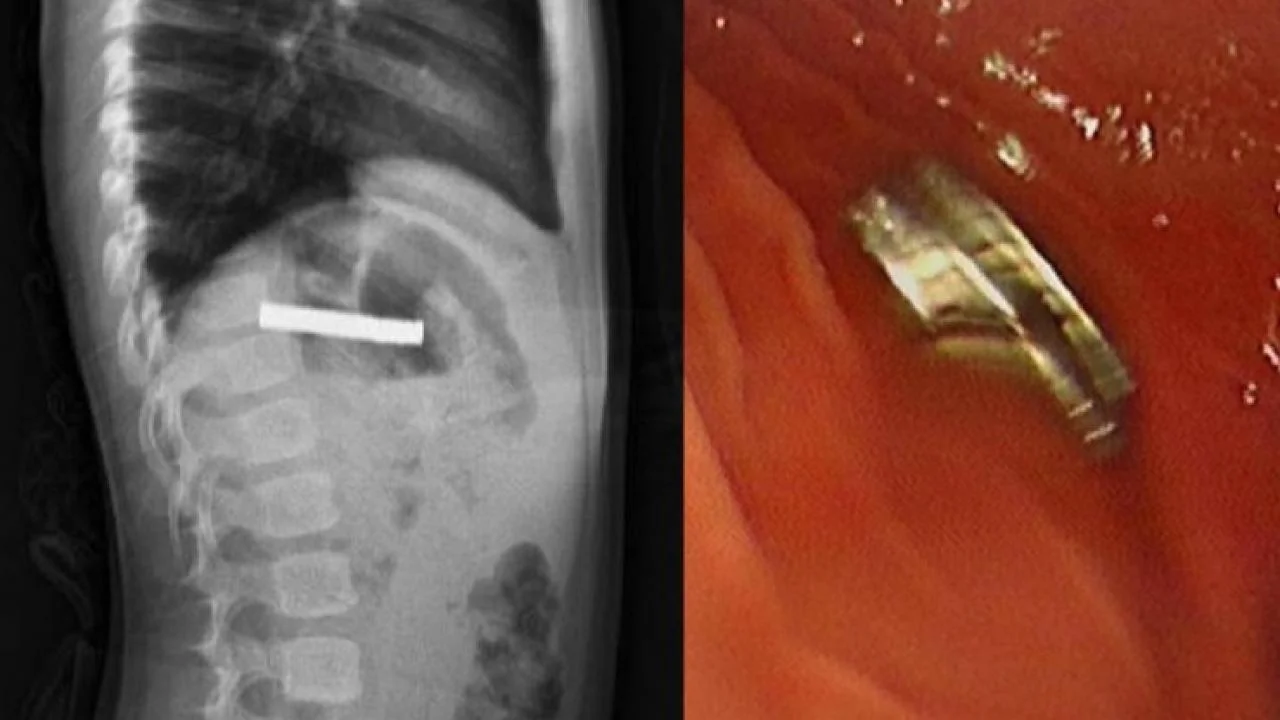

Fırat Üniversitesi Çocuk Gastroenteroloji Hepatoloji ve Beslenme Bilim Dalı Başkanı Prof. Dr. Yaşar Doğan, yapılan tetkikler sonrası, çocuk hastanın yemek borusuna yapıştığı belirlenen 19 mıknatısı endoskopik yöntemle çıkararak başarılı bir operasyona imza attı.

Mıknatıslar uzun süre yemek borusunda takılı kaldığı için yemek borusu ve mide girişinde zedelenmeler olurken, çocuğun sağlık durumunun iyi olduğu ve taburcu edildiği öğrenildi.